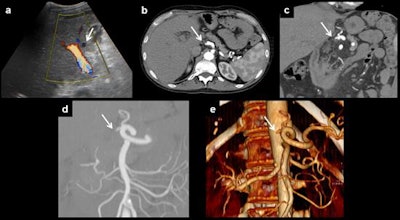

Anastomotic thrombosis. Artery thrombosis, the most serious complication of orthotopic liver transplantation, can be demonstrated as an absence of flow on Doppler ultrasound (a). CT can depict the thrombus and also the absence of distal flow (b). Multiplanar reconstructions and volume rendering images can be useful to ensure diagnosis (c-e). All images courtesy of Dr. Juan-José Delgado-Moraleda and Insights into Imaging.The reported incidence of vascular complications is around 7% for cadaveric donor liver transplantation and around 13% for living donor liver transplantation, the authors wrote. Vascular abnormalities are associated with a high incidence of graft loss and mortality.